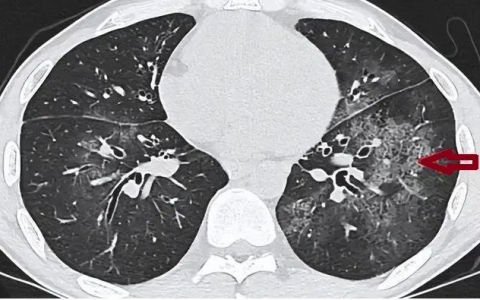

(3)社区获得性肺炎:由肺炎链球菌(仅指对青霉素敏感的菌株,包括合并菌血症的病例)、流感嗜血杆菌(仅指β-内酰胺酶阴性菌株)或卡他莫拉球菌引起者。